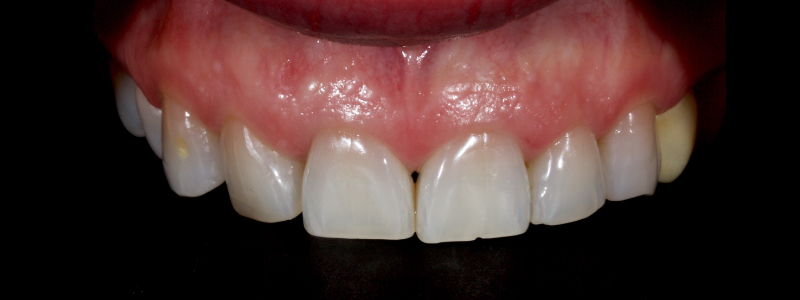

The anterior teeth had lost around 25% of the coronal structure, and dentin was exposed (Figs. 1–3). The patient requested a minimally invasive solution.

After deprogramming with a splint and occlusal equilibration, the anterior teeth were restored with direct composite resin using a minimal prep approach (Figs. 4 and 5). The occlusal scheme was idealized (Fig. 6).